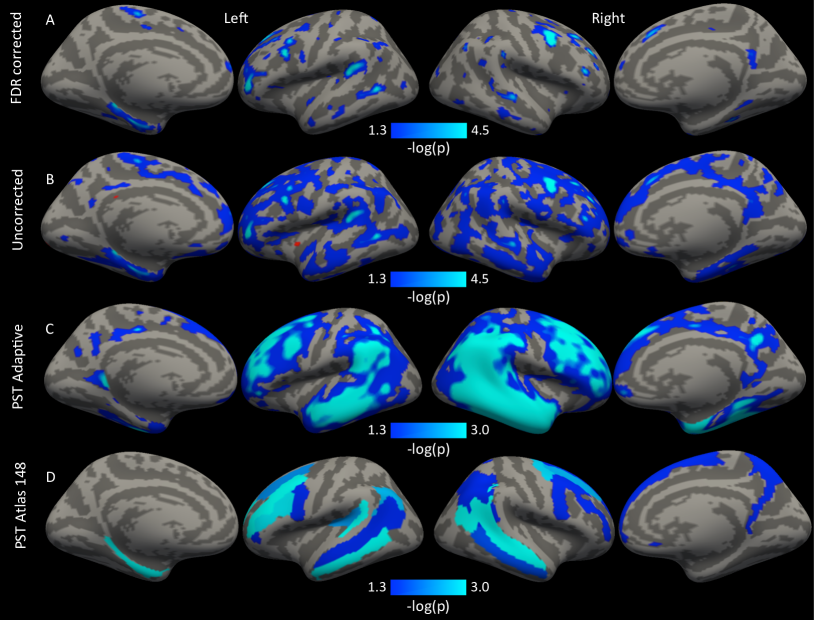

For the vertex-wise analyses, we use the software package Freesurfer to perform Benjamini-Hochberg (BH) correction separately across each hemisphere (Figure 1 A). The spatial extent of the FDR-corrected results is more limited than what we might expect given the very strong association between diagnosis and average cortical thickness. Uncorrected exploratory analyses were conducted to further identify regions related to the whole-brain results (Figure 1 B). The most significant results occur in left and right frontal lobes. These analyses suggest that thinning in larger portions of the frontal and temporal lobes is associated with increased risk of MCI; however, these results are not found using a method that guarantees control of the FWER or FDR.

Results suggest that thinner cortex in bilateral temporal and frontal lobes and right precuneus is associated with an increased risk of MCI (Figure 1 C & D). Results are given as where is obtained using the simulated distribution (21). These locations are known to be thinner in AD versus HC as well as in AD versus MCI (Singh et al., 2006) and the results here demonstrate that there are significant differences between MCI and HC in the same region. The results indicate that the degree of frontal and temporal lobe thinning is correlated with diagnostic severity, and suggest that measurements of cortical thickness may provide useful information over neurospsychological scales in identifying people at risk for AD. Differences in these regions between MCI and HC were previously shown by Wang et al. (2009); however the authors did not control for multiple comparisons or adjust for covariates.

To reiterate, the blue areas in Figure 1 C & D are based on low-rank inference and control the FWER of the projected scores. The procedure has improved power over standard correction methods seen in Figure 1 A & B by performing inference in a lower dimensional space. The p-values obtained in Figures 1 and 2 use (21) and indicate the probability of observing a projected score statistic as extreme under the global null . Though interpretation is restricted to the projected scores, the results align strongly with previous reports (Singh et al., 2006; Wang et al., 2009).